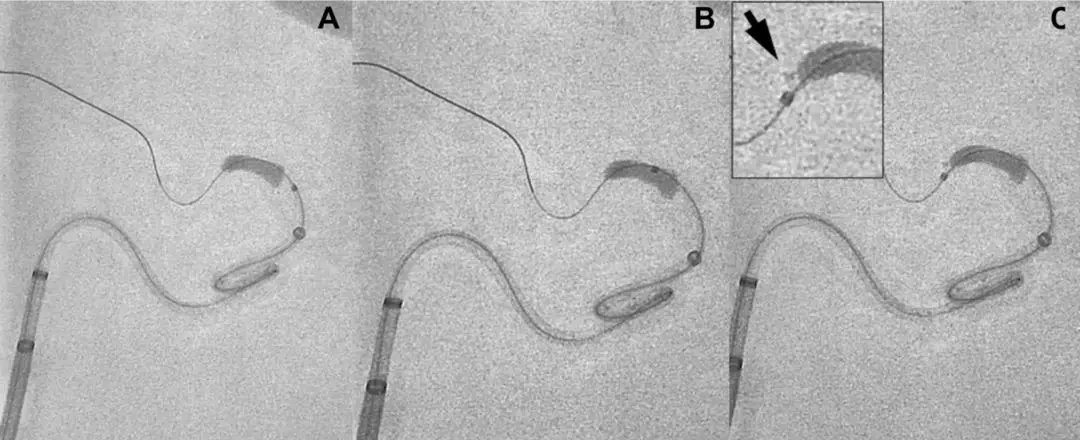

图1:微导管穿越血栓,随后撤出导丝,使用300ml盐水缓慢冲洗微导管收集血栓残片(箭头)

该研究制作了可视化的大脑中动脉血栓模型,并利用3种不同尺寸的微导管(Pro18、XT-27、3MAX)穿越血栓来模拟取栓过程。血栓为通过凝血酶诱导产生的牛血血栓,长度、直径分别为6mm、4.3mm。

首先,采用Synchro-14导引导丝穿越血栓团块,然后,通过不同外径的微导管:Trevo Pro18(OD=2.4F)、Excelsior XT-27(OD=2.7F)、3MAX(OD=3.8F),每种尺寸的微导管重复试验9次。